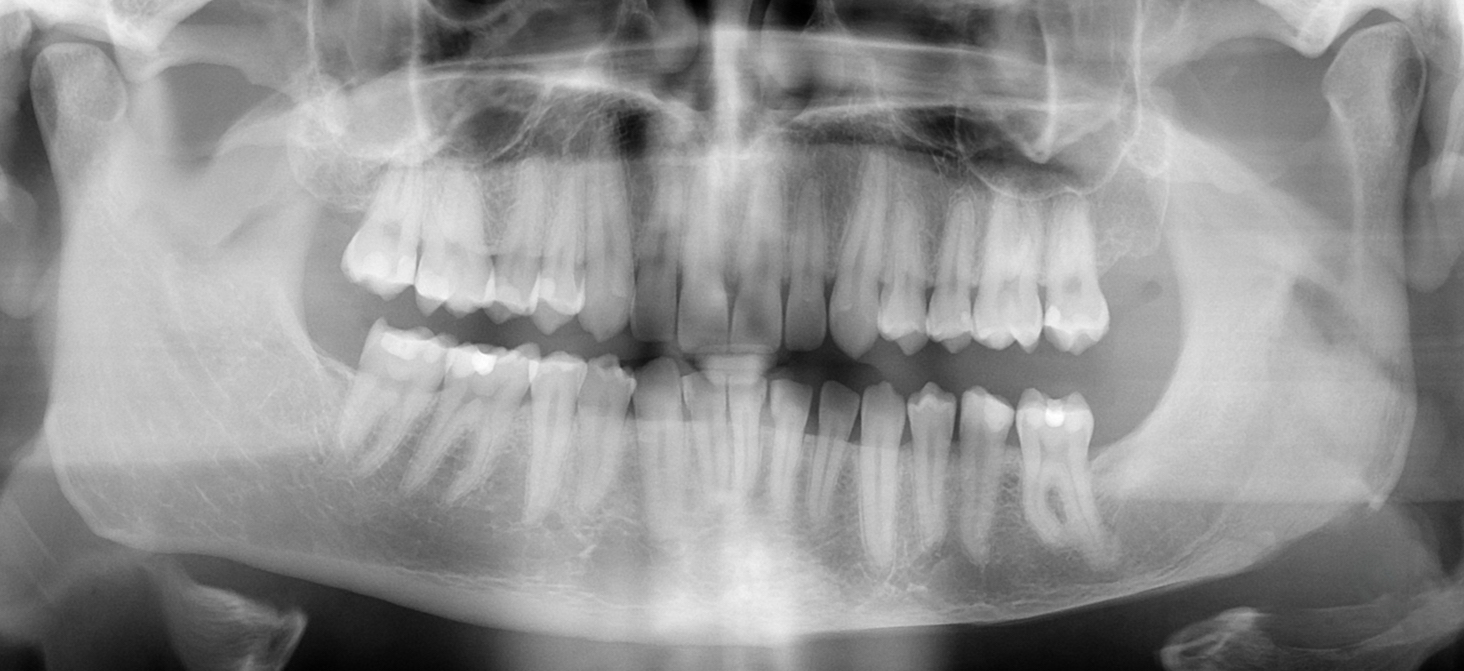

panoramic x ray after corrective jaw surgery Corrective jaw surgery Jawline X Ray The various head and neck cancers. Diagnosis of a fractured jaw: Many conditions can cause a lump on your jawline, and most aren’t serious. Jaw cancer is a rare type of head and neck cancer and one of many types of oral cancer. A healthcare professional will conduct a physical examination to assess the. When should i be worried about. Jawline X Ray.

Xray of a girls jawline taken with a panoramic poster Zazzle Jawline X Ray Most types of jaw cancer have spread to the jaw through the tooth sockets, tongue, salivary glands, palate, or the floor of the mouth. Many conditions can cause a lump on your jawline, and most aren’t serious. A healthcare professional will conduct a physical examination to assess the. The various head and neck cancers. When should i be worried about. Jawline X Ray.

Panoramic Dental XRay of Childs Teeth Development Stock Photo Alamy Jawline X Ray An easy way to check how wide your mouth can open is to try to put 3 fingers vertically between your lower and upper front teeth. The various head and neck cancers. Jaw cancer can affect either the lower jaw, called the mandible, or the upper jaw, the maxilla. Most types of jaw cancer have spread to the jaw through. Jawline X Ray.